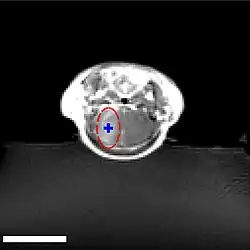

Sur le modèle animal de la souris, on a utilisé des ultrasons focalisés dans le domaine de 0,5 à 2 MHz[139], avec de brèves impulsions de l'ordre de la milliseconde, répétées à intervalles de 1 s, pour une durée totale inférieure à une minute[140]. La fréquence optimale se situe au-dessous de 1 MHz[141]. La puissance acoustique instantanée est inférieure au watt, et donc la puissance moyenne de l'ordre du mW. Les microbulles utilisées sont en général des microbulles autorisées pour l'échocardiographie de contraste. Elles ont typiquement un diamètre de 3 à 5,5 μm, et sont composées typiquement d'albumine humaine, remplie d'octafluoropropane ou de gaz lourd semblable[142].